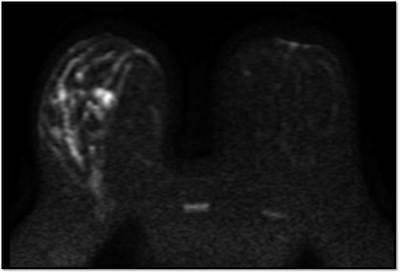

MG: Right breast shows focal asymmetric density in lateral quadrant extending for an area of 12.4 x 6.5 cm with no associated discrete mass or suspicious calcifications. Correlative ultrasound showed a heterogeneous area with echogenic vascular surrounding parenchyma in lateral quadrant with no discrete solid masses. MRI breast was performed on day 14 of LMP. Right breast shows an area predominantly consisting of fat in lateral quadrant extending for an area of 1.2×5.5x 8.9 cm along its maximum AP, ML and CC dimensions. This area is bright on fat suppressed T2 sequences and shows significant restriction on diffusion weighted sequences. There is rapid and progressive non mass enhancement in the above area extending anteriorly in to the nipple and posteriorly into the pectoralis major muscle. Two large and tortuous feeding vessels are seen to arise from the subclavian and axillary arteries respectively. Right breast shows predominantly fat containing mass showing abnormal enhancement described. The possibilities include vascular neoplasm or remotely fat necrosis. Ultrasound guided core biopsy was Suggestive of an inflammatory lesion, possibly fat necrosis. However enlarged and tortuous feeding arteries to the vascular mass was worrisome and we recommended an excision biopsy correlation. Excision biopsy showed “Multiple patchy areas of dense inflammatory infiltration in a background of fat necrosis”.